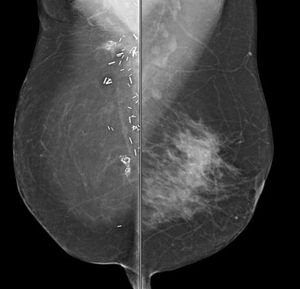

49-year-old patient presented for bilateral screening mammogram as well as bilateral screening ultrasound due to dense breast tissue.